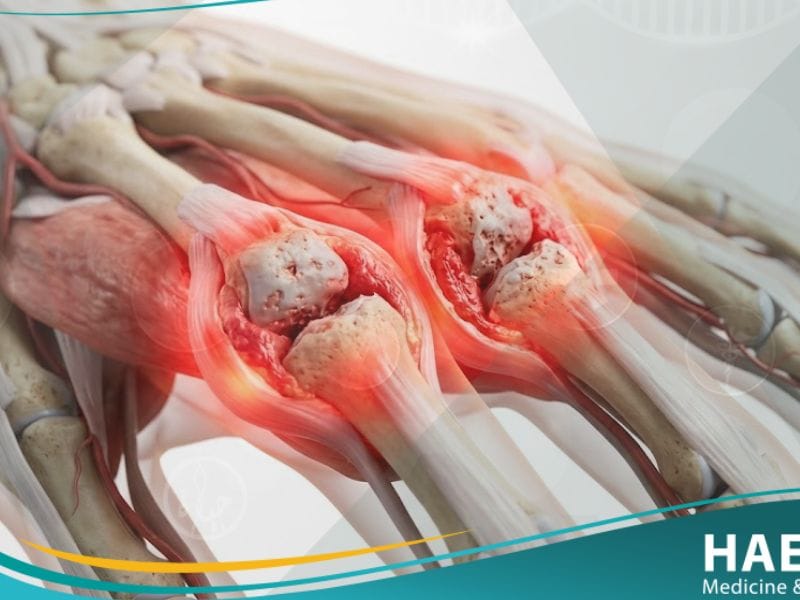

يعرف التهاب المفاصل الروماتويدي بأنه حالة مرضية يهاجم فيها الجهاز المناعي عن طريق الخطأ غشاء “السينوفيم” (Synovium) الذي يحيط بالمفاصل، مما ينتج عنه تضخم وسماكة في هذا الغشاء. يوضح موقع حياة الطبي أن هذا الالتهاب المزمن يؤدي في نهاية المطاف إلى تدمير الغضاريف والعظام داخل المفصل، مما يتسبب في ارتخاء الأربطة وضعف العضلات المحيطة.

- التورم والدفء المفصلي: تظهر المفاصل المصابة بـ التهاب المفاصل الروماتويدي بشكل متضخم ومنتفخ، مع شعور بحرارة موضعية عند لمس المنطقة المصابة نتيجة زيادة التروية الدموية للالتهاب.

لا يتوقف تأثير التهاب المفاصل الروماتويدي عند حدود المفاصل، بل يمتد ليكون مرضاً جهازياً قد يؤثر على العمر الافتراضي وجودة الحياة بشكل عام إذا لم يتم التحكم به.